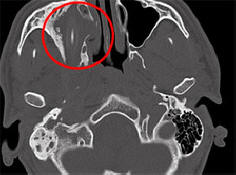

Jotkut sairaudet ja vammat ovat niin huomaamatta, että henkilö voi elää heidän kanssaan vuosia epäilemättä heitä olemassaolon. Kuten amerikkalainen, joka vei melkein kaksi vuotta oman aivojen nestevuoto vuotavalle nenälle, Saksan kansalainen onnistui elää 15 vuotta lyijykynällä päällään, raportoi Spiegel. Kuten yliopistollisen sairaalan edustajat sanoivat Aachen, Nordrhein-Westfalen, 24-vuotias afgaanisaksalainen alkuperä tuli heille auttamaan vuonna 2011. nuori henkilö valitti jatkuvista päänsärkyistä, vilustumisesta ja pahenemisesta näkö toisessa silmässä. Kauan aikaa lääkärit eivät voineet ymmärtää mitä tapahtui. ei tehnyt tietokonetomografiaa. Kävi ilmi, että päässäni koko ajan potilas oli kymmenen sentin lyijykynä. Hän on joka sijaitsee suoraan nuoren miehen oikean silmän pistorasian yläpuolella ja asetetaan siihen paine. Saksalainen, joka halusi pysyä nimettömänä, ei pystynyt selittämään mistä kynä tuli hänen päähänsä, mutta muisti myöhemmin kuinka epäonnistuneesti laski lapsuudessa. Lääkärit poistivat vieraan kehon päästä nuoria miehiä, ja hän toipui pian. Vasta toukokuun lopussa, melkein vuoden kuluttua leikkauksen jälkeen lääkärit päättivät omistautua tähän tapaukseen erillinen konferenssi, jonka avulla toimittajat oppivat siitä. Tämä ei ole ensimmäinen kerta, kun henkilö on onnistunut jo pitkään elää kehossa vieraan esineen kanssa. Joten vuonna 2007 vanha saksalainen nainen, joka kärsii päänsärkystä ja nenäverenvuodosta, he poistivat kynän, joka oli ollut siellä 50 vuotta.